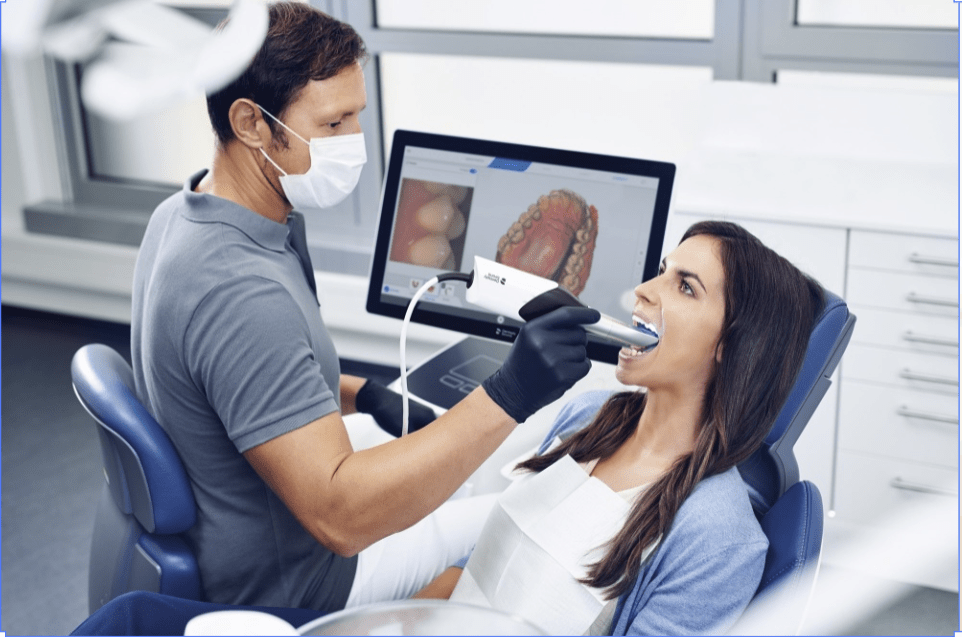

- digital scanner